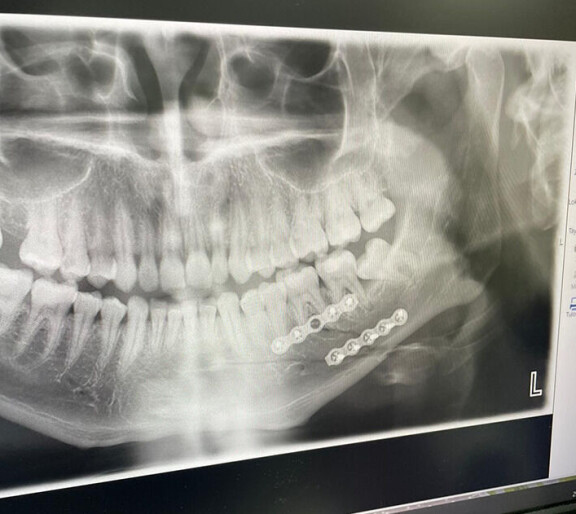

Mikan leukaan on asennettu levyt, jotka tukevat leukaa murtuman parantumisen aikana.